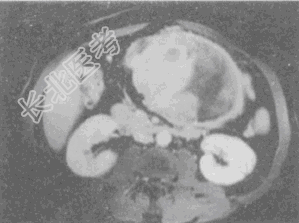

- 单项选择题男,36岁, 腹胀、消化不良、消瘦、中上腹痛,影像检查如下图, 最可能的诊断是

A、胃间质肉瘤并肝转移

B、胃间质瘤并原发性肝癌

C、内胚窦瘤肝转移

D、胃淋巴瘤伴原发性肝癌

E、胃间质瘤并肝血管瘤